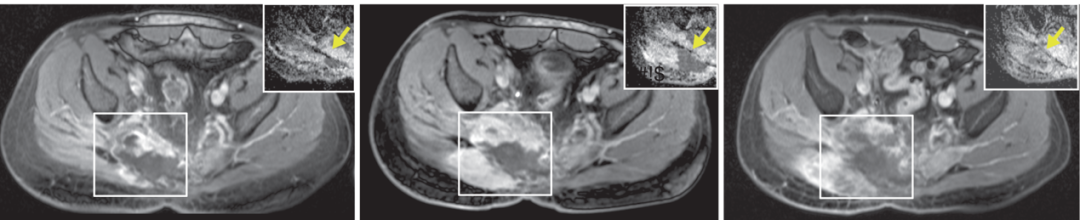

图2. 应用Olaparib治疗脊索瘤发生耐药性。a.Olaparib治疗7个月(疾病稳定;左图)和10个月(疾病进展;右图)后的MRI成像。b.在进展时活检取样,行全基因组测序。通过Sanger测序发现PARP1外显子20中的错义突变。c、d、e.与DNA结合的p.T910A突变PARP1的结构图。